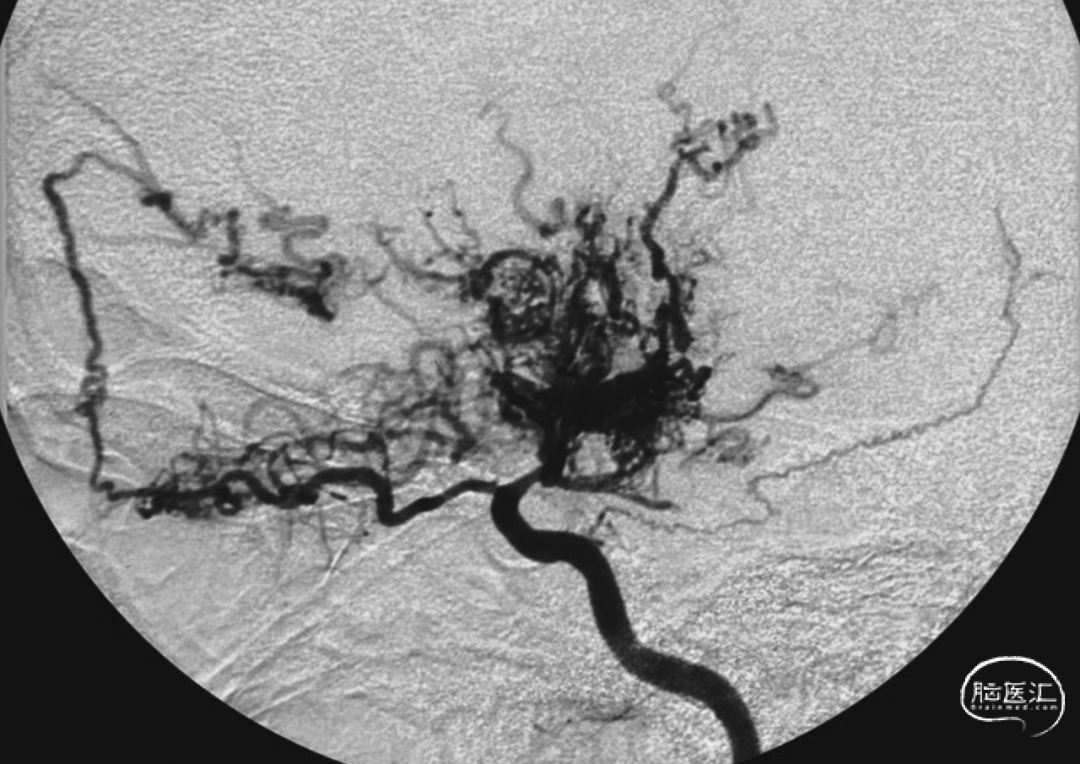

直接的颅内外动脉搭桥嘛,就是直接把颈外动脉的分支和缺血的脑半球里的皮质动脉连起来。间接的血运重建呢,就是拿颈外动脉分支供血的那些组织,转移到缺血的脑半球表面,让它和下面的皮质血管搞个侧支循环,好让缺血区恢复供血。